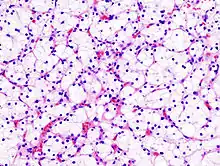

Generally, the cells have a clear cytoplasm, are surrounded by a distinct cell membrane and contain round and uniform nuclei.

Microscopically, CCRCCs are graded by the ISUP/WHO as follows:[1][2]

- Grade 1: Inconspicuous and basophilic nucleoli at magnification of 400 times

- Grade 2: Clearly visible and eosinophilic nucleoli at magnification of 400 times

- Grade 3: Clearly visible nucleoli at magnification of 100 times

- Grade 4: Extreme pleomorphism or rhabdoid and/or sarcomatoid morphology

Clear-cell renal-cell carcinoma. HE, × 100

Clear-cell renal-cell carcinoma. Fuhrman grade = 1. HE, × 400

Grade 3: Arrows point at a clearly visible nucleolus.